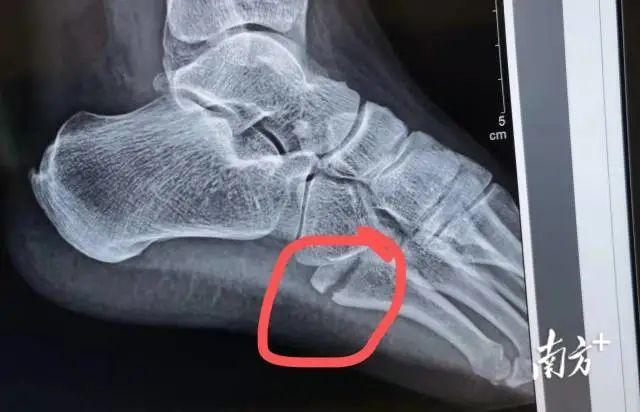

事实上,当天从采样点撤下来,黄恒一身冷汗,回到医院,拍片一看,左足第5趾骨基底部骨折。医生让她马上住院,消肿后手术。如果不马上治疗,会导致脚部肿胀加重、骨折移位,将来可能影响肢体的功能。

3月16日中午,尚剑主任亲自主刀,黄恒在关节创伤科顺利做完左足第5跖骨骨折内固定手术,打入了2枚钢钉。